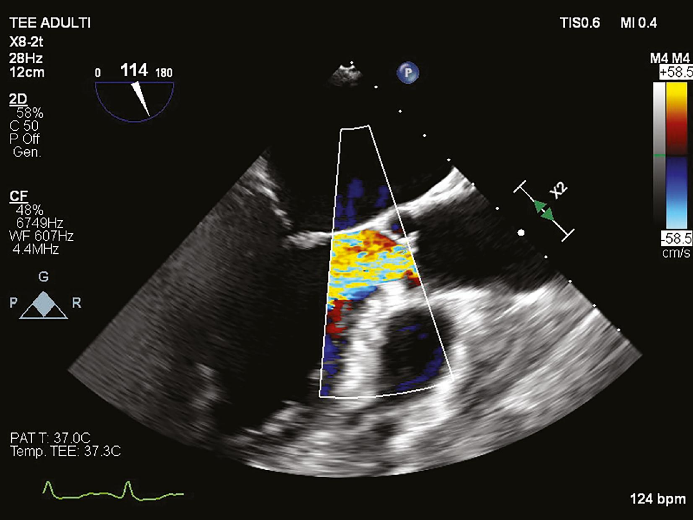

一名 54 岁的女性患者于 2024 年 2 月首次到他们诊所就诊,主诉为劳力性呼吸困难。患者无合并症,否认药物使用和吸烟史。心电图显示患者左心室肥厚。经胸超声心动图示:1)左心室增大,心室壁厚度正常(舒张末期直径 54 mm,室间隔 10 mm,后壁 10 mm,舒张末期容积指数 66 mL/m2); 2)收缩功能保留,舒张功能受损,射血分数 65%,主动脉瓣中心性反流导致重度主动脉关闭不全,主动脉根部和升主动脉尺寸正常,没有其他瓣膜异常。术前经食管超声心动图 (TEE)显示主动脉瓣四叶式畸形,根据 Hurwitz 和 Roberts分型被归类为 A 型,其特征是四个完全相等的瓣叶。计算机断层扫描 (CT) 证实了四叶式主动脉瓣并排除了冠状动脉疾病。